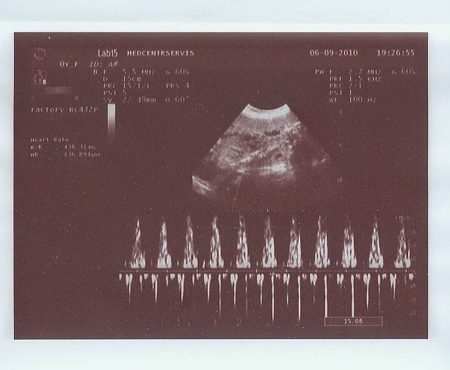

СДО:

1) АП 3,5

2) ПМА 1,75

3) ЛМА 1,8

3) А это, по-моему, доплер